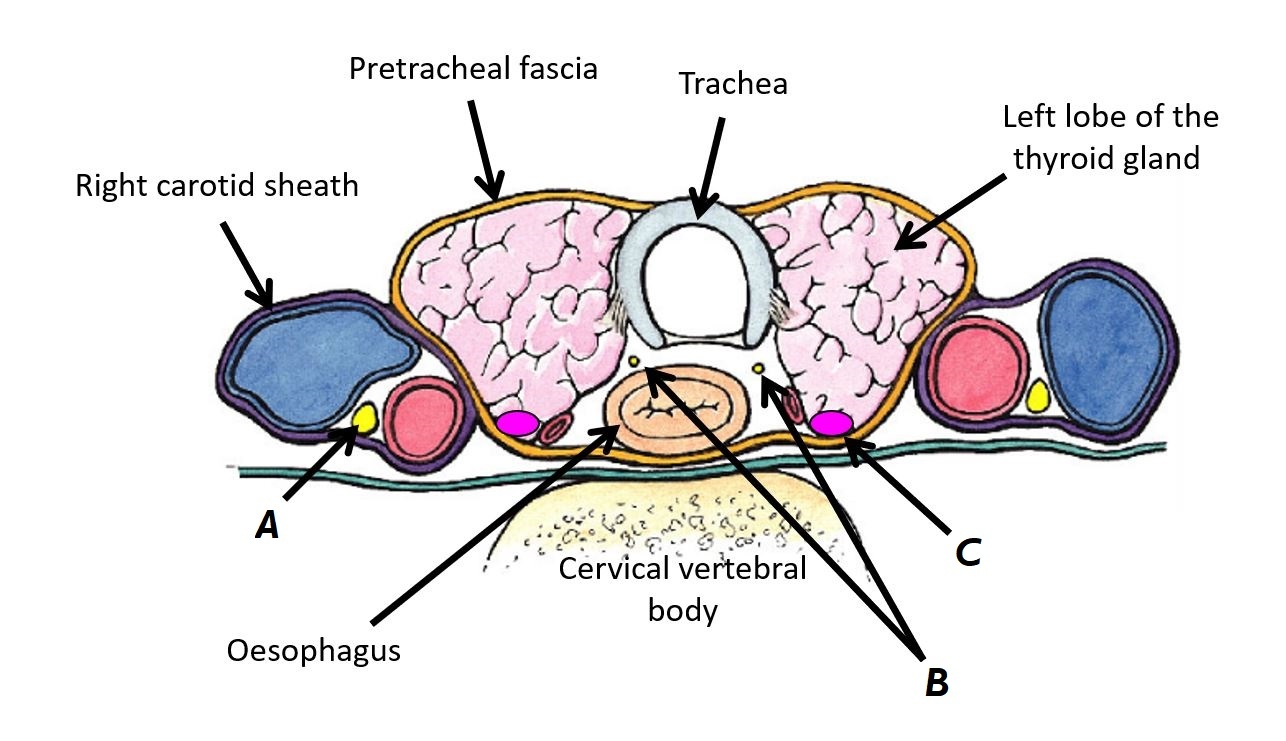

Name structures A, B and C

A - Right carotid sheath

B - Pretracheal fascia

C - Left lobe of thyroid gland